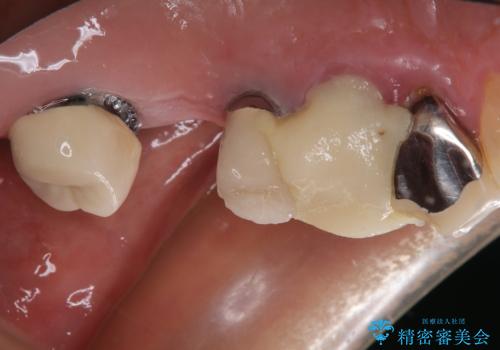

歯がボロボロで抜歯が必要な状態であり、後方にはインプラントが埋入されているため、同様にインプラントによる補綴治療を行うこととしました。

プラスチックを外すと同時に抜歯を行い、1ヶ月ほど待機して歯肉が落ち着いたことを確認してから速やかにインプラントを埋入することとしました。

従来は4ヶ月ほど待機してからの埋入が一般的でしたが、歯肉の炎症が落ち着いた時点で速やかに埋入できるようになり、4ヶ月の短期間で治療を終えることができました。